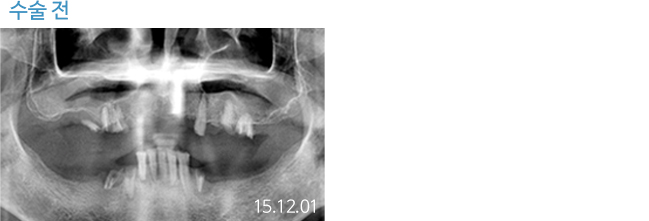

한 번 잘 심으면 10년 뒤에도 끄떡없는

더와이즈 임플란트

첨단 장비를 이용한 정확한 진단, 안정성이 입증된 정품 재료 사용,

노하우가 풍부한 숙련된 의료진의 시술 등이 임플란트 수명을 결정합니다.

※ 실제 본원에서 치료 받은 환자의 동의를 얻어 게재했습니다.

개인의 특성에 따라 부작용이 발생할 수 있으므로 담당의와 충분히 상의하시길 바랍니다.